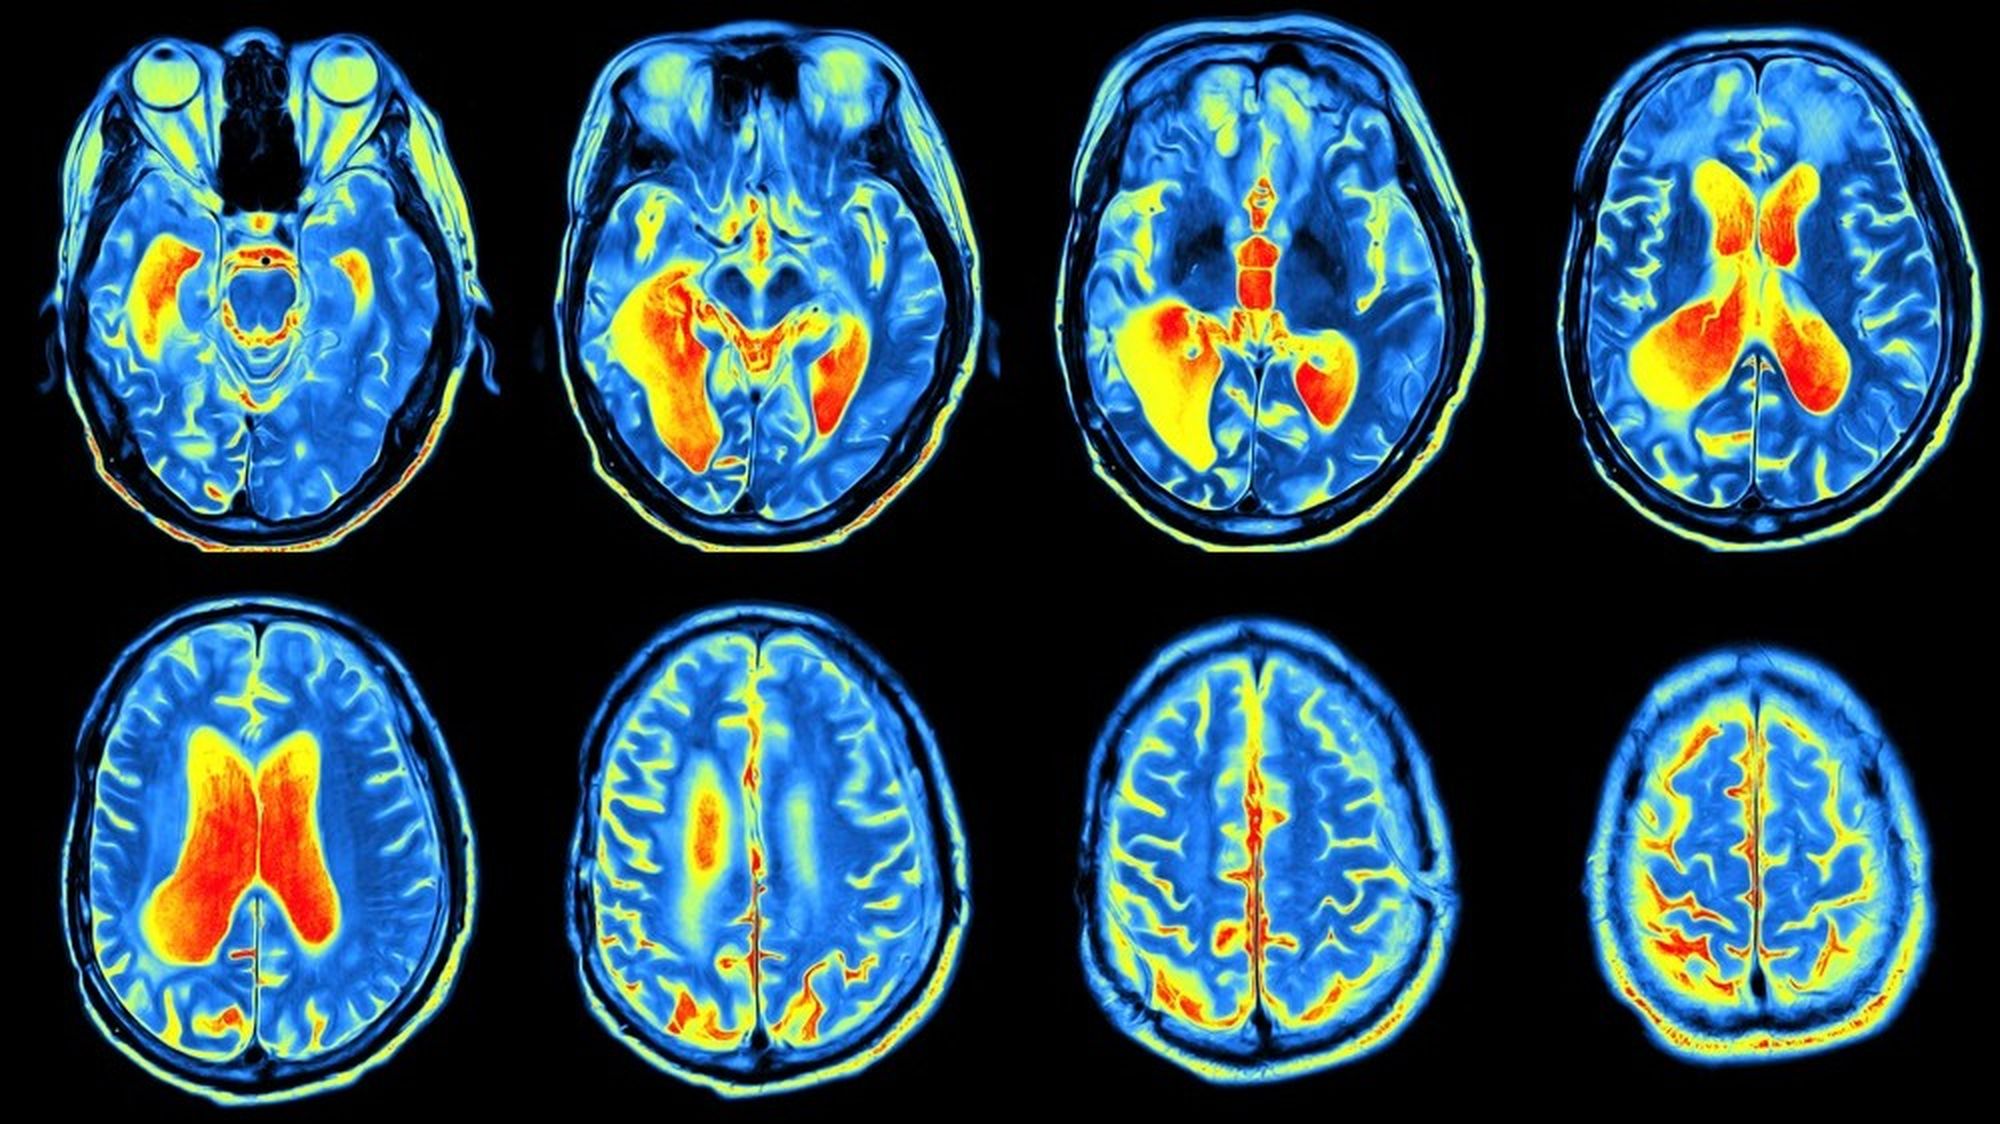

- PET taraması, pozitron anhilasyonu sonucu oluşan gama ışınlarını tespit ederek parlak bölgeler oluşturur ve bu sayede hastalıkların yayılımı, tedavi etkinliği ve tekrarlaması izlenebilir.

Vücuda verilen ilaçtaki radyoaktif izleyicilerin, pozitron anhilasyonu (elektron ve karşıt maddesi olan pozitronun birbirlerini yok edişi) sonucu saçtığı gama dalgaları, PET tarayıcısı tarafından tespit edilir. İlacı absorbe eden dokular, yaptıkları bu ışıma dolayısıyla tarama sonucunda parlak bölgeler hâlinde görülür. Taramada görülen renk ve parlaklık farklılıkları, farklı derecelerdeki doku fonksiyonlarına işaret eder. Bu sayede doktorlar, tedavide nasıl bir yol izleneceğine karar verir. Sadece Amerika Birleşik Devletleri'nde her yıl yaklaşık olarak 2 milyon PET taraması yapılmaktadır.

Glikoz, beynin en temel yakıtıdır. PET taramaları için hazırlanan ilaçlardaki izleyiciler, glikoz ve benzeri bileşiklere tutturulur. Bu şekilde tarayıcı, radyoaktif glikozu görüntüleyerek beynin en fazla oranda glikoz kullandığı bölgeleri tespit eder.